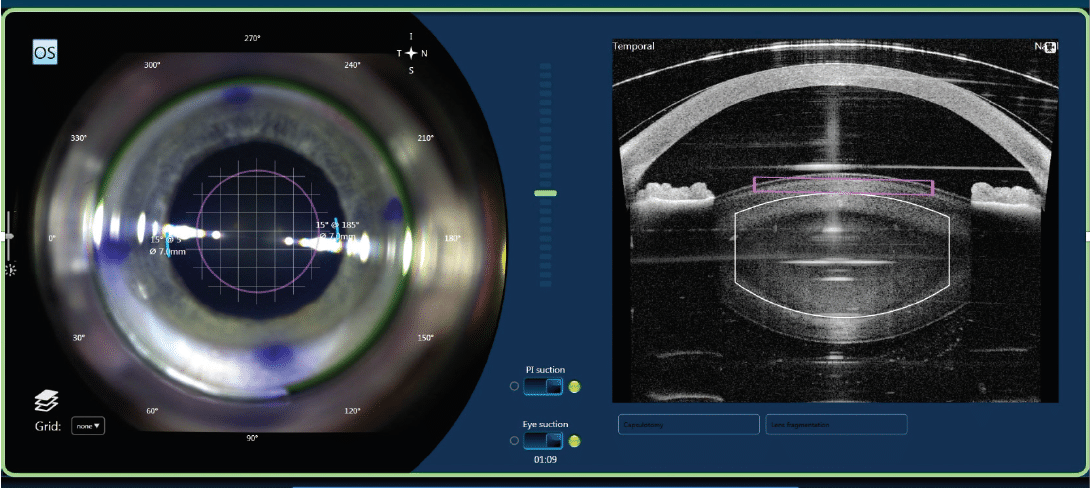

La chirurgia della cataratta laser è guidata da immagini dettagliate e monitoraggio in tempo reale durante la procedura. Il livello di dettaglio delle immagini fornito dallo strumento aiuta il chirurgo ad effettuare l'intervento in estrema sicurezza. Puoi stare tranquillo sapendo che stai scegliendo la procedura più avanzata disponibile per curare il tuo occhio.